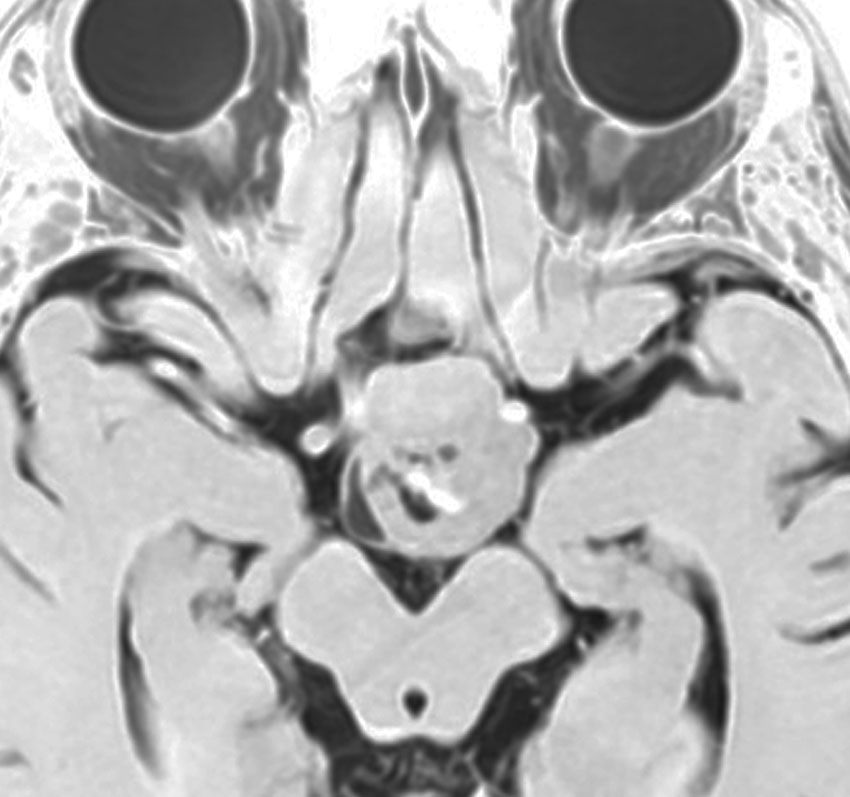

7歳の子の小脳虫部腫瘍です。左と中央のMRIをみると一見,髄芽腫に見えます。でもこれは毛様細胞性星細胞腫で,手術で全部取れて,後遺症もなく治りました(右側)。inverted T2(左側のCISS)では黒く(低信号)に写って小脳との境界が明瞭です。

T1強調画像のガドリニウム増強(左)ではわかりませんが,右のT2強調画像で腫瘍部分がとても白く(強い高信号)に写っているのが,最大の特徴です。多くの場合,T2強調画像で毛様細胞性星細胞腫の診断がつきます。このようなT2でかなり強い高信号になるものは毛様粘液性星細胞腫の成分を含むことが多いです。